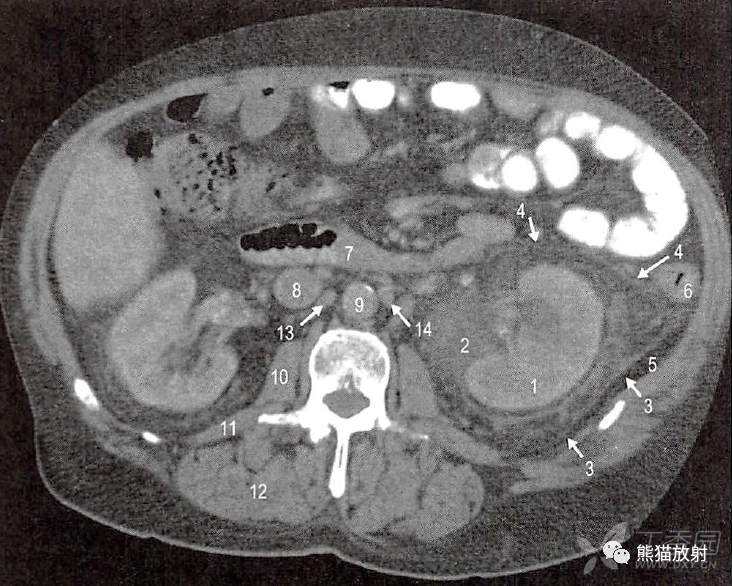

A.第2腰椎水平横断面;1.胰颈;2.前部气体的集聚(描述出胰周间隙);3.后部集聚的积液和碎片(描绘出胰周间隙);4.胰腺后融合筋膜(肾前筋膜融合十二指肠系膜右叶);5.胰周筋膜与左结肠系膜右叶融合;6.胰周筋膜深面到左结肠系膜前和收缩的小网膜囊;7.胃床上胰周前筋膜与小网膜囊腹膜融合;8.肠系膜上动脉;9.腹主动脉;10.下腔静脉;11.左肾静脉;12.左肾实质;13.左肾周间隙(不能与左肾后旁隙区分开);14.右肾实质;15.右肾周间隙(不能与右肾旁后间隙区别);16.第2腰椎体上部;17.脾曲;18.胃(被积液抬起或挤压);19.胆囊;20.肝右叶(5和6段);21.右膈脚;22.腰大肌起点;23.左侧腰方肌;24.左竖脊肌。